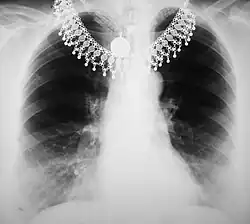

The overall effect of tissue attenuation is illustrated in the Figure 3.9 for the case of a chest radiograph. The exposed area of the patient consists in simplistic terms of air, tissues and bone and is surrounded by the rectangular collimator leaves. The air provides relatively negligible attenuation, while the bone provides substantial attenuation - and tissues provide an intermediate amount. As a result, bone can generate relatively high attenuation at lower X-ray energies and their X-rays shadows can interfere with the visualisation of the lung fields. Increasing the X-ray energy, by increasing the kV, will increase bone penetrability and reduce their shadowing effect. The overall result is a change in the prominence of features associated with different regions in the image histogram.

A typical image is shown in Figure 3.10. It can be seen that bone has a brighter shade of grey than that of the enveloping tissue and is brighter still than the surrounding air. This is the conventional method of displaying a radiograph such that higher photon attenuation is encoded as a brighter shade of grey.